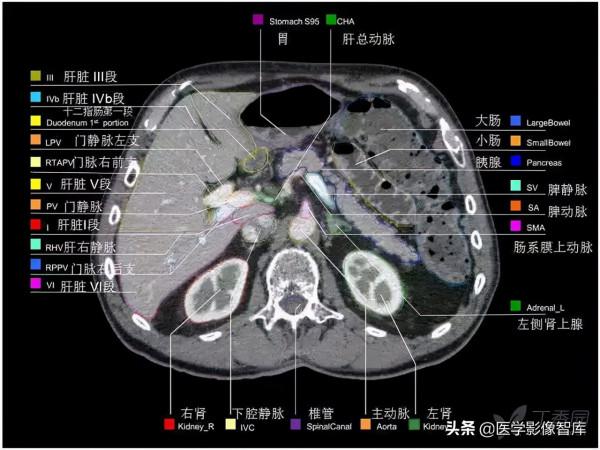

腹部CT